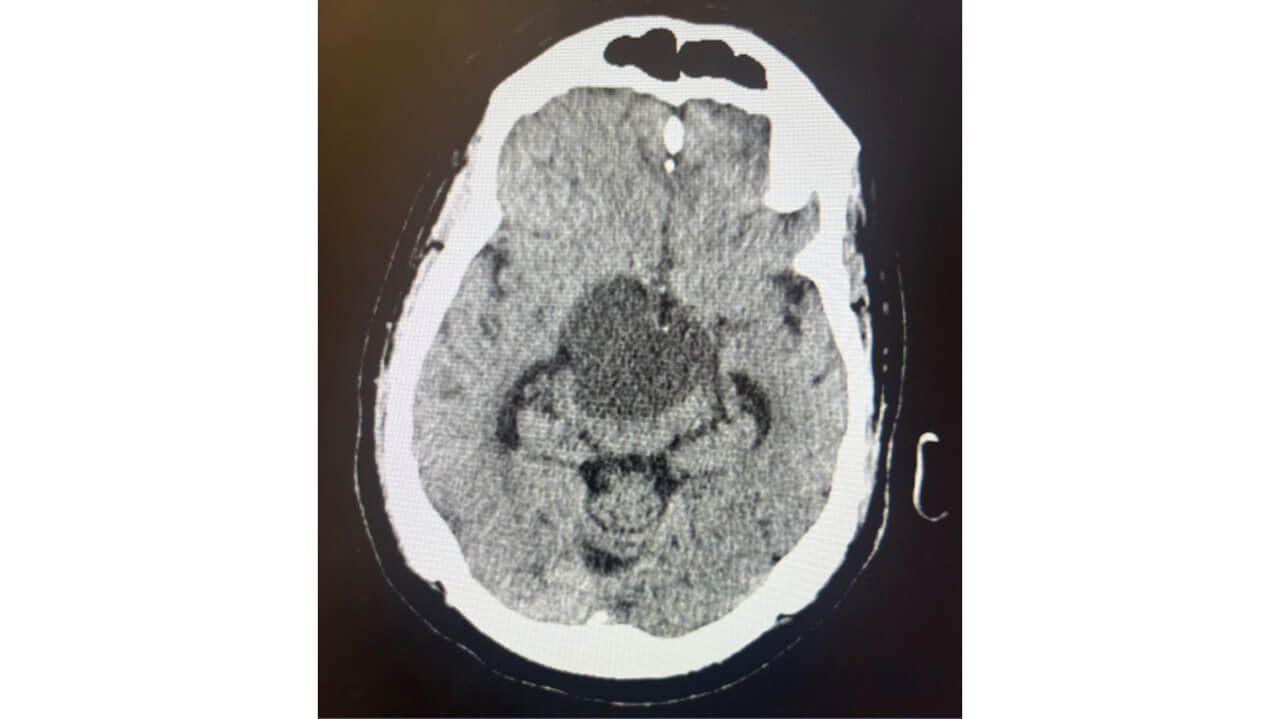

CT head w/o contrast 10/13 11am

• Recurrent soft tissue tumor in the suprasellar cistern measuring 4.0 x 4.5 cm​

• Exerting mass effect on the third ventricle with borderline increased ventricular volume ​

CT head w/o contrast 10/13 10pm

• Findings are concerning for obstructive hydrocephalus

CT head w/o contrast 10/17​

• Sellar / suprasellar lesion has decreased in size now measuring approximately 3.6 x 3.1 cm​

• Repeat head CT w/o contrast demonstrated decreased size of the ventricular system​

• Sella and suprasellar lesion now measuring 3.6 x 3.1 cm in size​